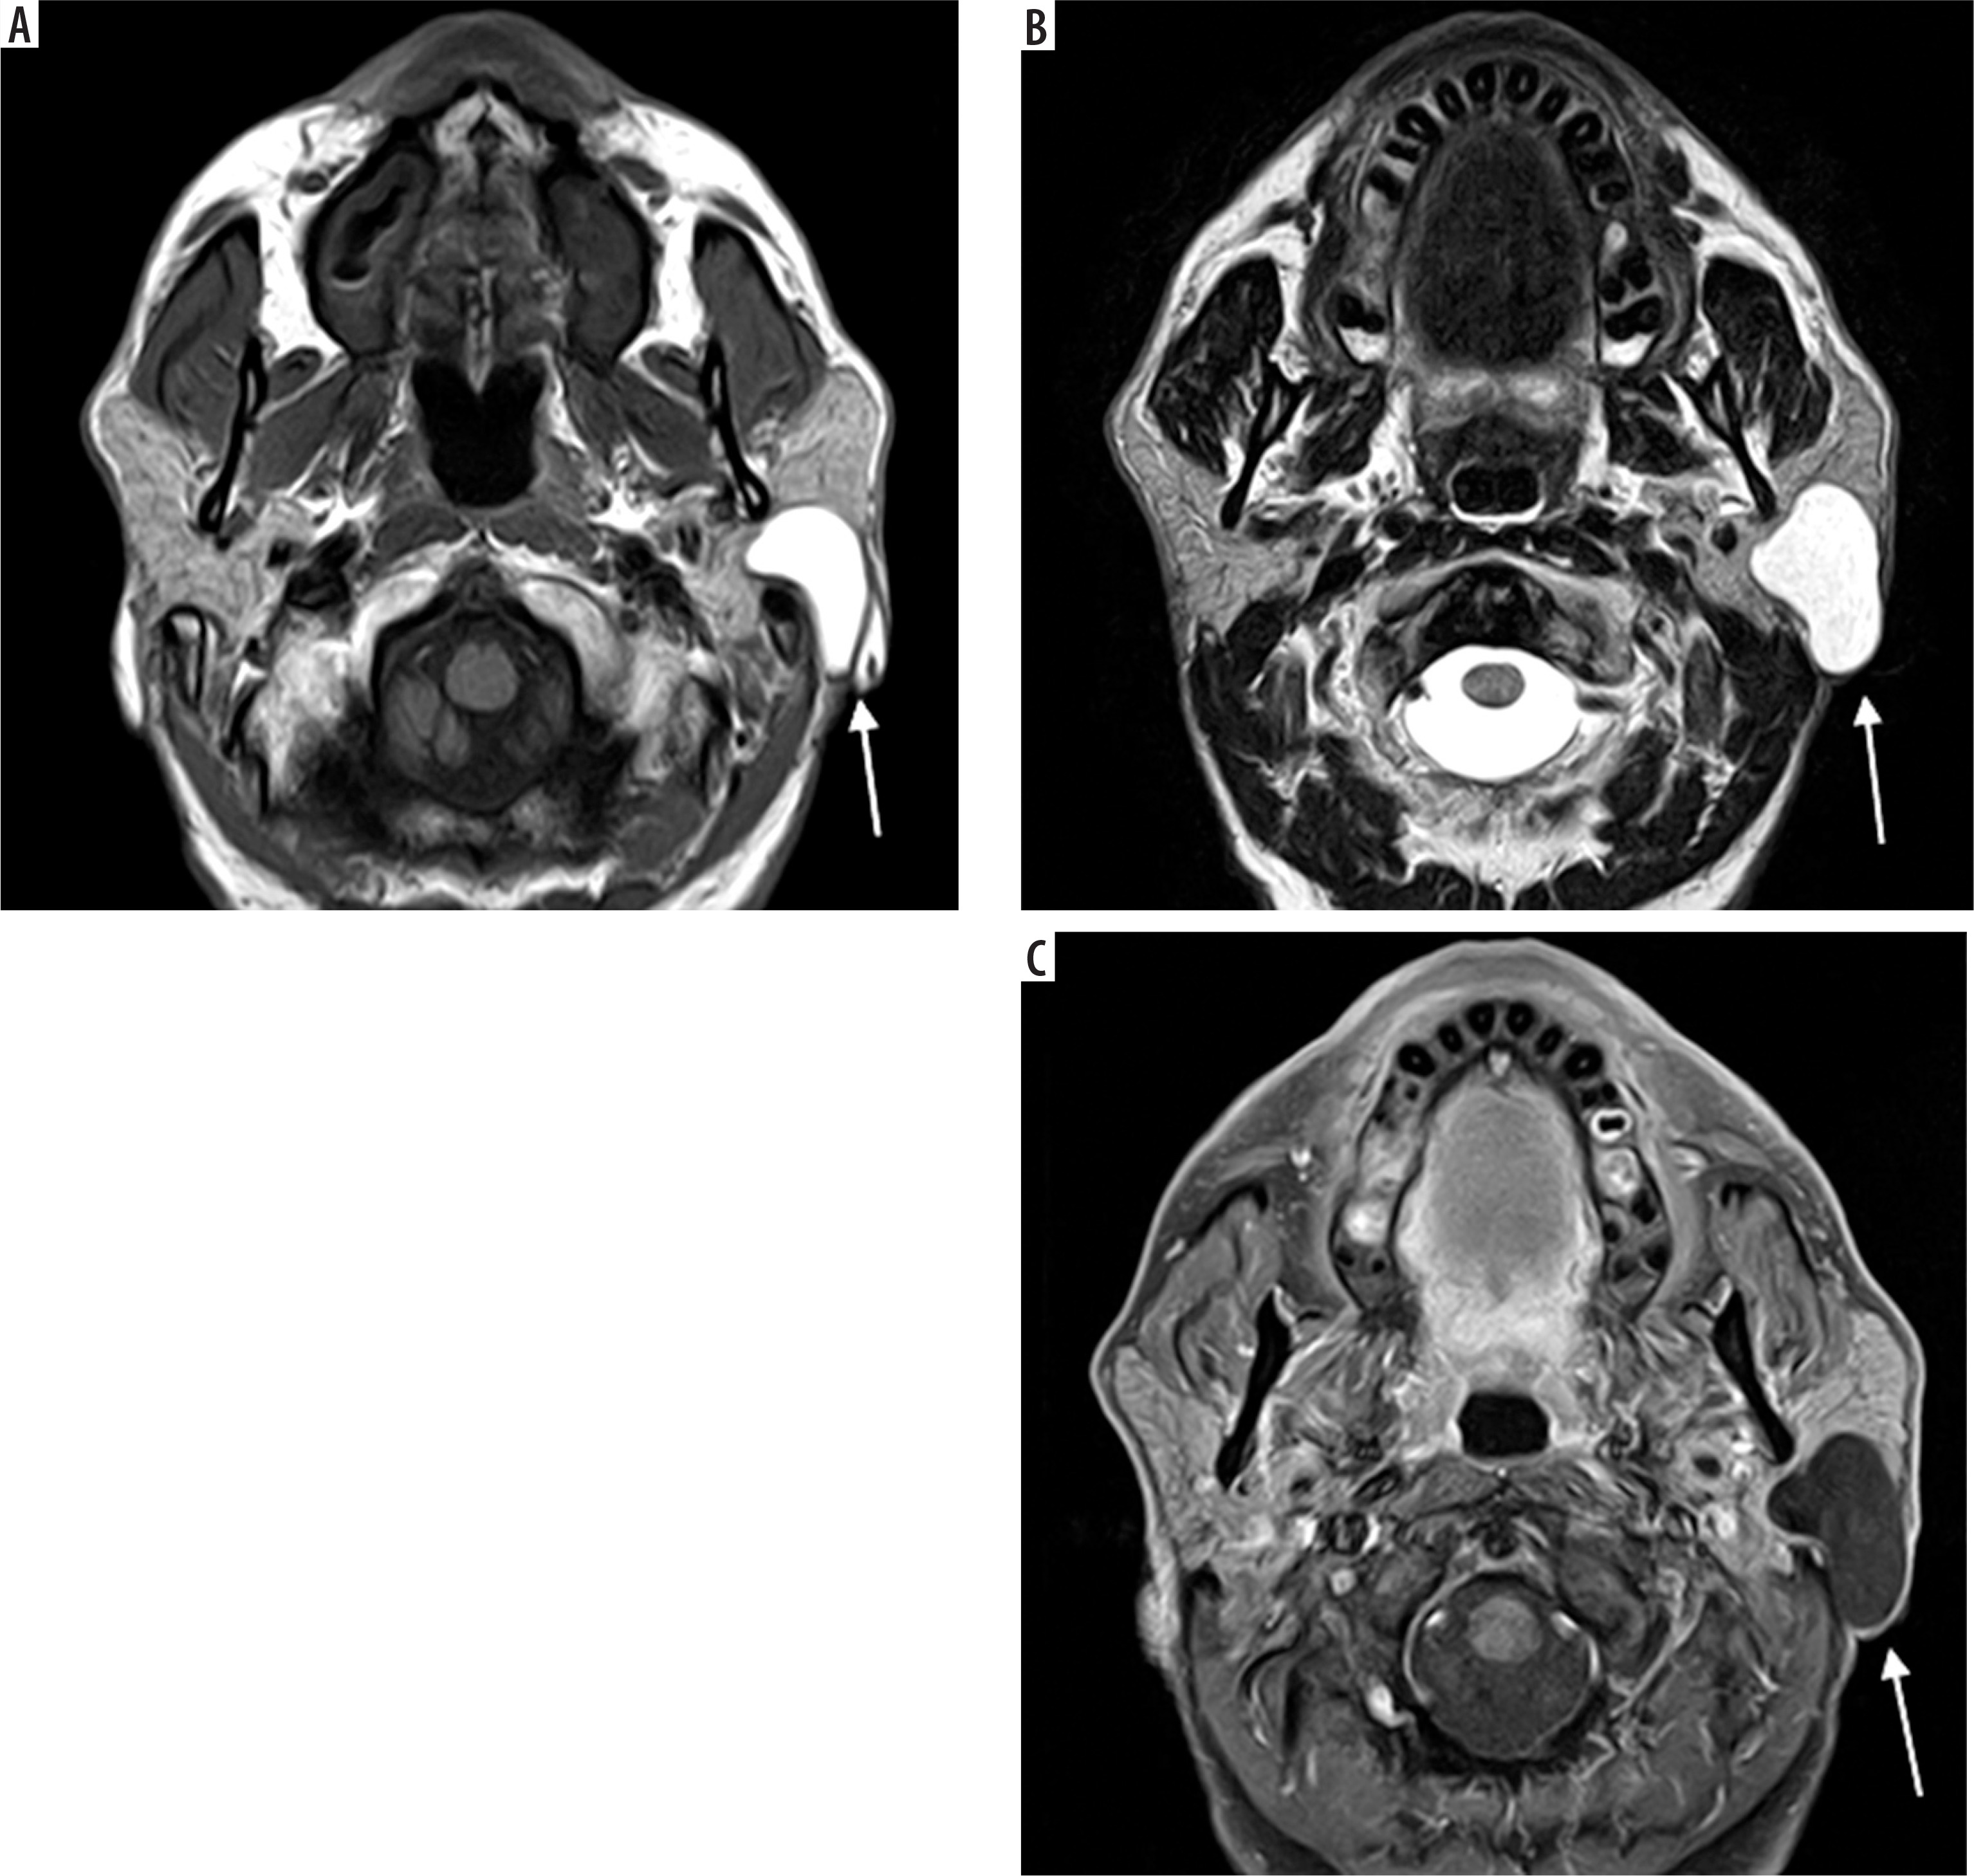

Case 3: Facial haemangioma

A 30-year-old female presented with a painless swelling in the left cheek. Coronal T2-weighted MRI imaging revealed a small, lobulated soft tissue mass in the left facial region measuring approximately 36 × 27 × 23 mm. The lesion was seen partially encasing the zygomatic bone and extending into the masseter muscle. On the T1-weighted post-contrast fat-saturated image (T1 C+ Fat Sat) (Figure 6B), the lesion appeared hyperintense due to the uptake of gadolinium-based contrast agent. The use of fat saturation suppresses the naturally high signal from fat, thereby enhancing visualisation of contrast-enhancing lesions. As a result, the lesion demonstrates clear enhancement against a suppressed background.

Figure 6

Coronal section of MRI of facial haemangioma: A) T2-weighted , B) T1 C+ Fat sat. These imaging features help confirm the vascular nature of the lesion, which is critical for surgical planning to minimise intraoperative bleeding and preserve surrounding structures [Courtesy: Radiopaedia. DOI: https://doi.org/10.53347/rID-81554, rID: 81554]

In contrast, the lesion appeared hypointense on the T2-weighted image, which is an atypical T2 appearance for a haemangioma (Figure 6A). This signal characteristic is consistent with a haemangioma that may have undergone secondary changes such as thrombosis, fibrosis, or calcification. These changes reduce the lesion’s fluid content, leading to a lower signal intensity on T2-weighted sequences.

Case 4: Tongue haemangioma

A 25-year-old female presented with a bluish nodule on the ventral aspect of the tongue. On MRI, the lesion appears well defined and isointense to mildly hypointense compared to the surrounding muscle on the T1-weighted image (Figure 7A). It demonstrates a classic hyperintense appearance on the T2-weighted sequence, a hallmark feature of fluid rich or vascular lesions (Figure 7B). Post-contrast, T1-weighted, fat-saturated (T1 C+ Fat sat) imaging shows strong enhancement of the lesion, confirming its vascular nature (Figure 7C).

Figure 7

Axial section of MRI of tongue haemangioma: A) T1-weighted, B) T2-weighted, C) T1 C+ Fat sat. These findings are essential for distinguishing haemangioma from other tongue masses and for assessing lesion extent and vascularity, which is critical for safe surgical excision and functional preservation [Courtesy: Radiopaedia. DOI: https://doi.org/10.53347/rID-84386, rID: 84386]